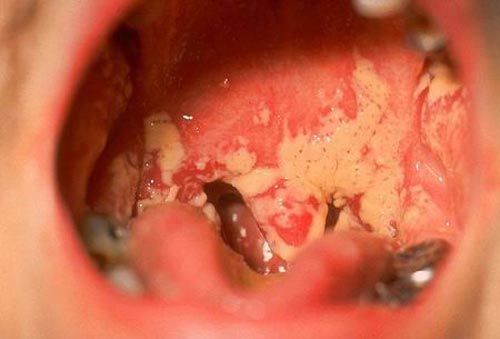

http://trungtamytehoavang.com.vn/question/sui-mao-ga-o-mieng-luoi-trieu-chung-hinh-anh-cach-chua/